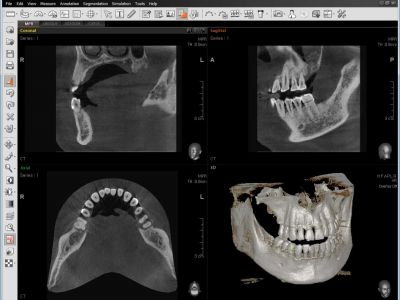

2D Y 3D EN UN VISOR

La visualización de imágenes 2D y 3D juntas proporcionan muchos beneficios. No es necesario utilizar dos programas de software diferentes y la función de un visor representa un aspecto profesional para sus pacientes.

Este diseño ayuda a los pacientes a comprender mejor las imágenes, lo que eventualmente dará como resultado un aumento de aceptación.

INNOVACIÓN INTELIGENTE PARA EL DIAGNÓSTICO EXACTO

La calidad de imágenes 3D ha mejorado dramáticamente gracias a la innovadora tecnología de reconstrucción de imagen.